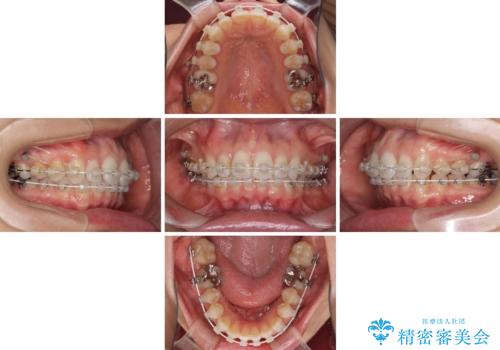

- 奥歯の虫歯と前歯のデコボコや突出感を気にして来院された患者様です。

上顎歯列が、下顎に対して前方にありましたが、口元に出っ歯の印象がなかったため、親知らずを抜歯した上で、上顎歯列全体を後方に移動させることとしました。

咬合力が強いため、アンカースクリューを使用し、ワイヤー装置にて矯正治療を行うこととしました。

上顎歯列を下顎に対して4mmほど移動させる必要があったため、治療は長期化することが予想されましたが、患者様にはこちらの期待以上にゴムかけなどに協力いただき、補綴治療も含めて2年強で終えることができました。